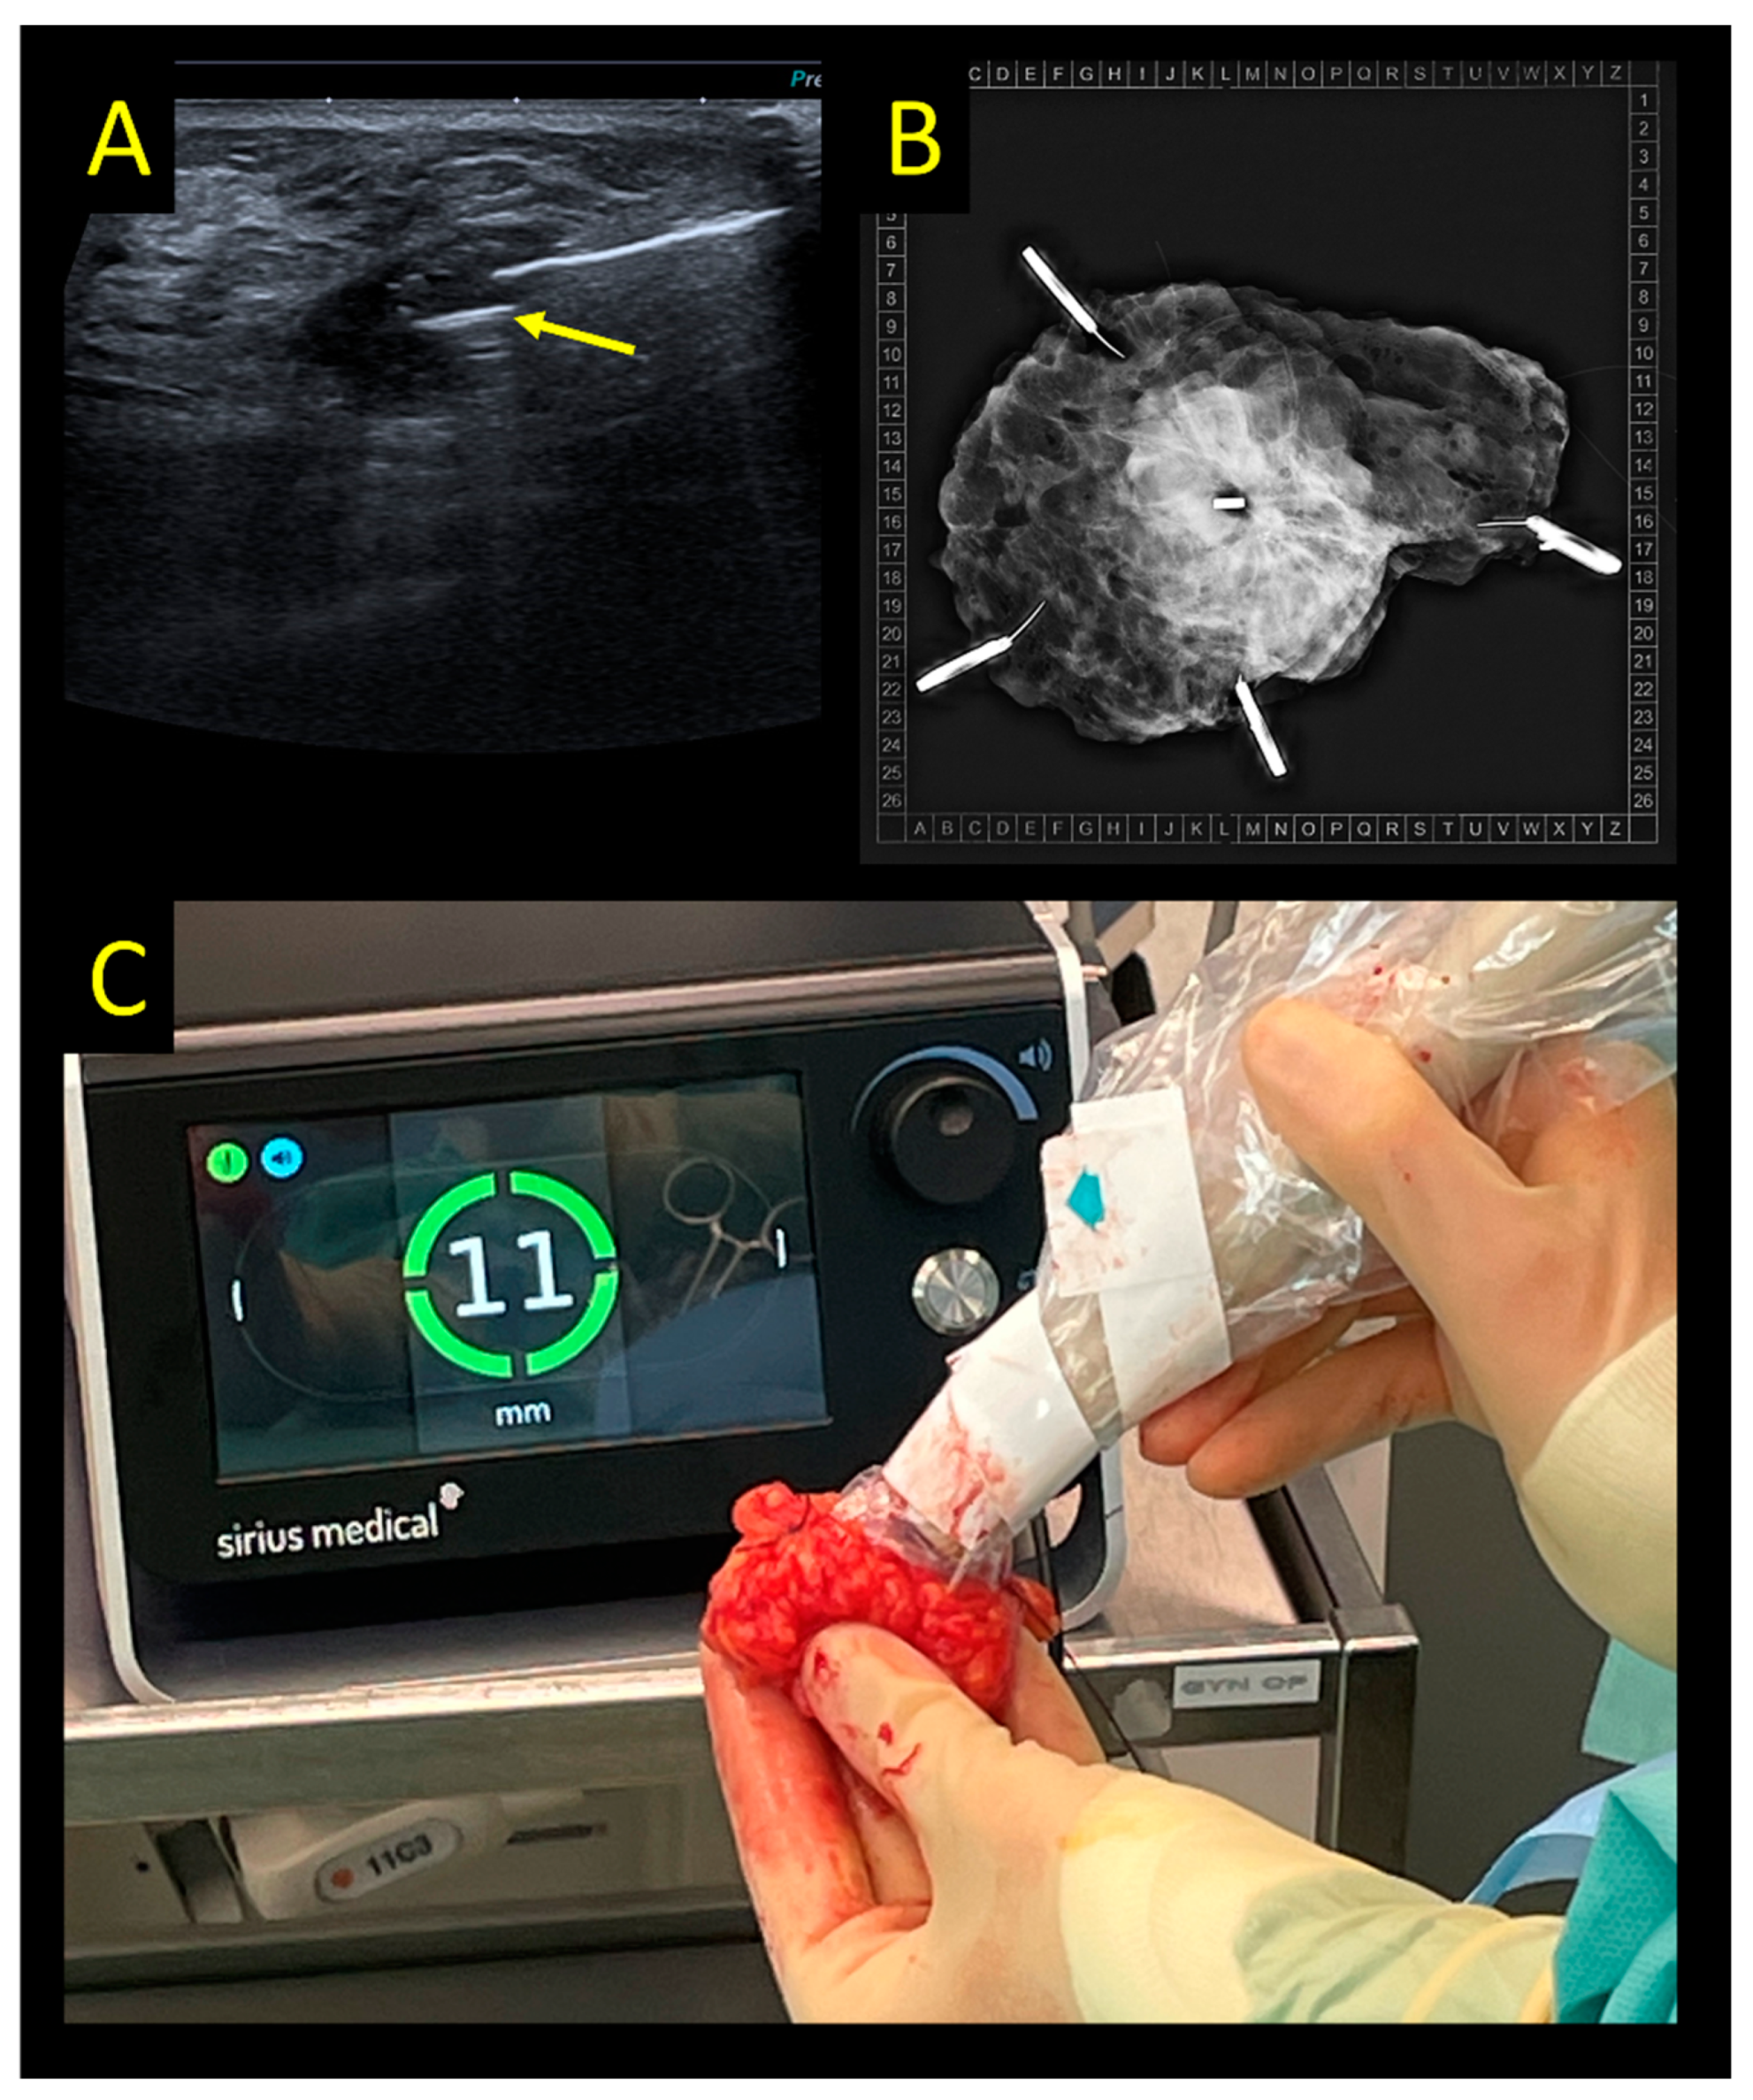

2.4. Sirius Pintuition

- Bessems, M.; van Breest Smallenburg, V.; van Bebber, I.; van Dijk, E.; van der Giessen, A.; Schermers, B.; Malloni, M. Safety and performance of Sirius Pintuition—A novel wire-free and non-radioactive localization system for breast cancer surgery. Eur. J. Surg. Oncol. 2022, 47, E1. [Google Scholar] [CrossRef]

- Clement, C.; Heeren, A.; den Hoed, I.; Jansen, P.; Venmans, A. First experience with Sirius Pintuition®—A novel magnetic localization system for breast cancer surgery. Eur. J. Surg. Oncol. 2022, 48, E70. [Google Scholar] [CrossRef]